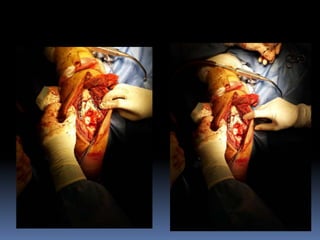

Este documento trata sobre las fracturas del tercio distal del húmero. Brevemente describe que representan el 0-5% de todas las fracturas, que la mayoría son del tipo C, y que pueden causar lesiones de tejidos blandos y nervios. Explica que en niños la línea de fractura suele ser supracondilea. Además, cubre temas como la anatomía relevante, mecanismos de lesión, clínica, diagnóstico, clasificación, y tratamiento quirúrgico y conservador de estas fracturas.